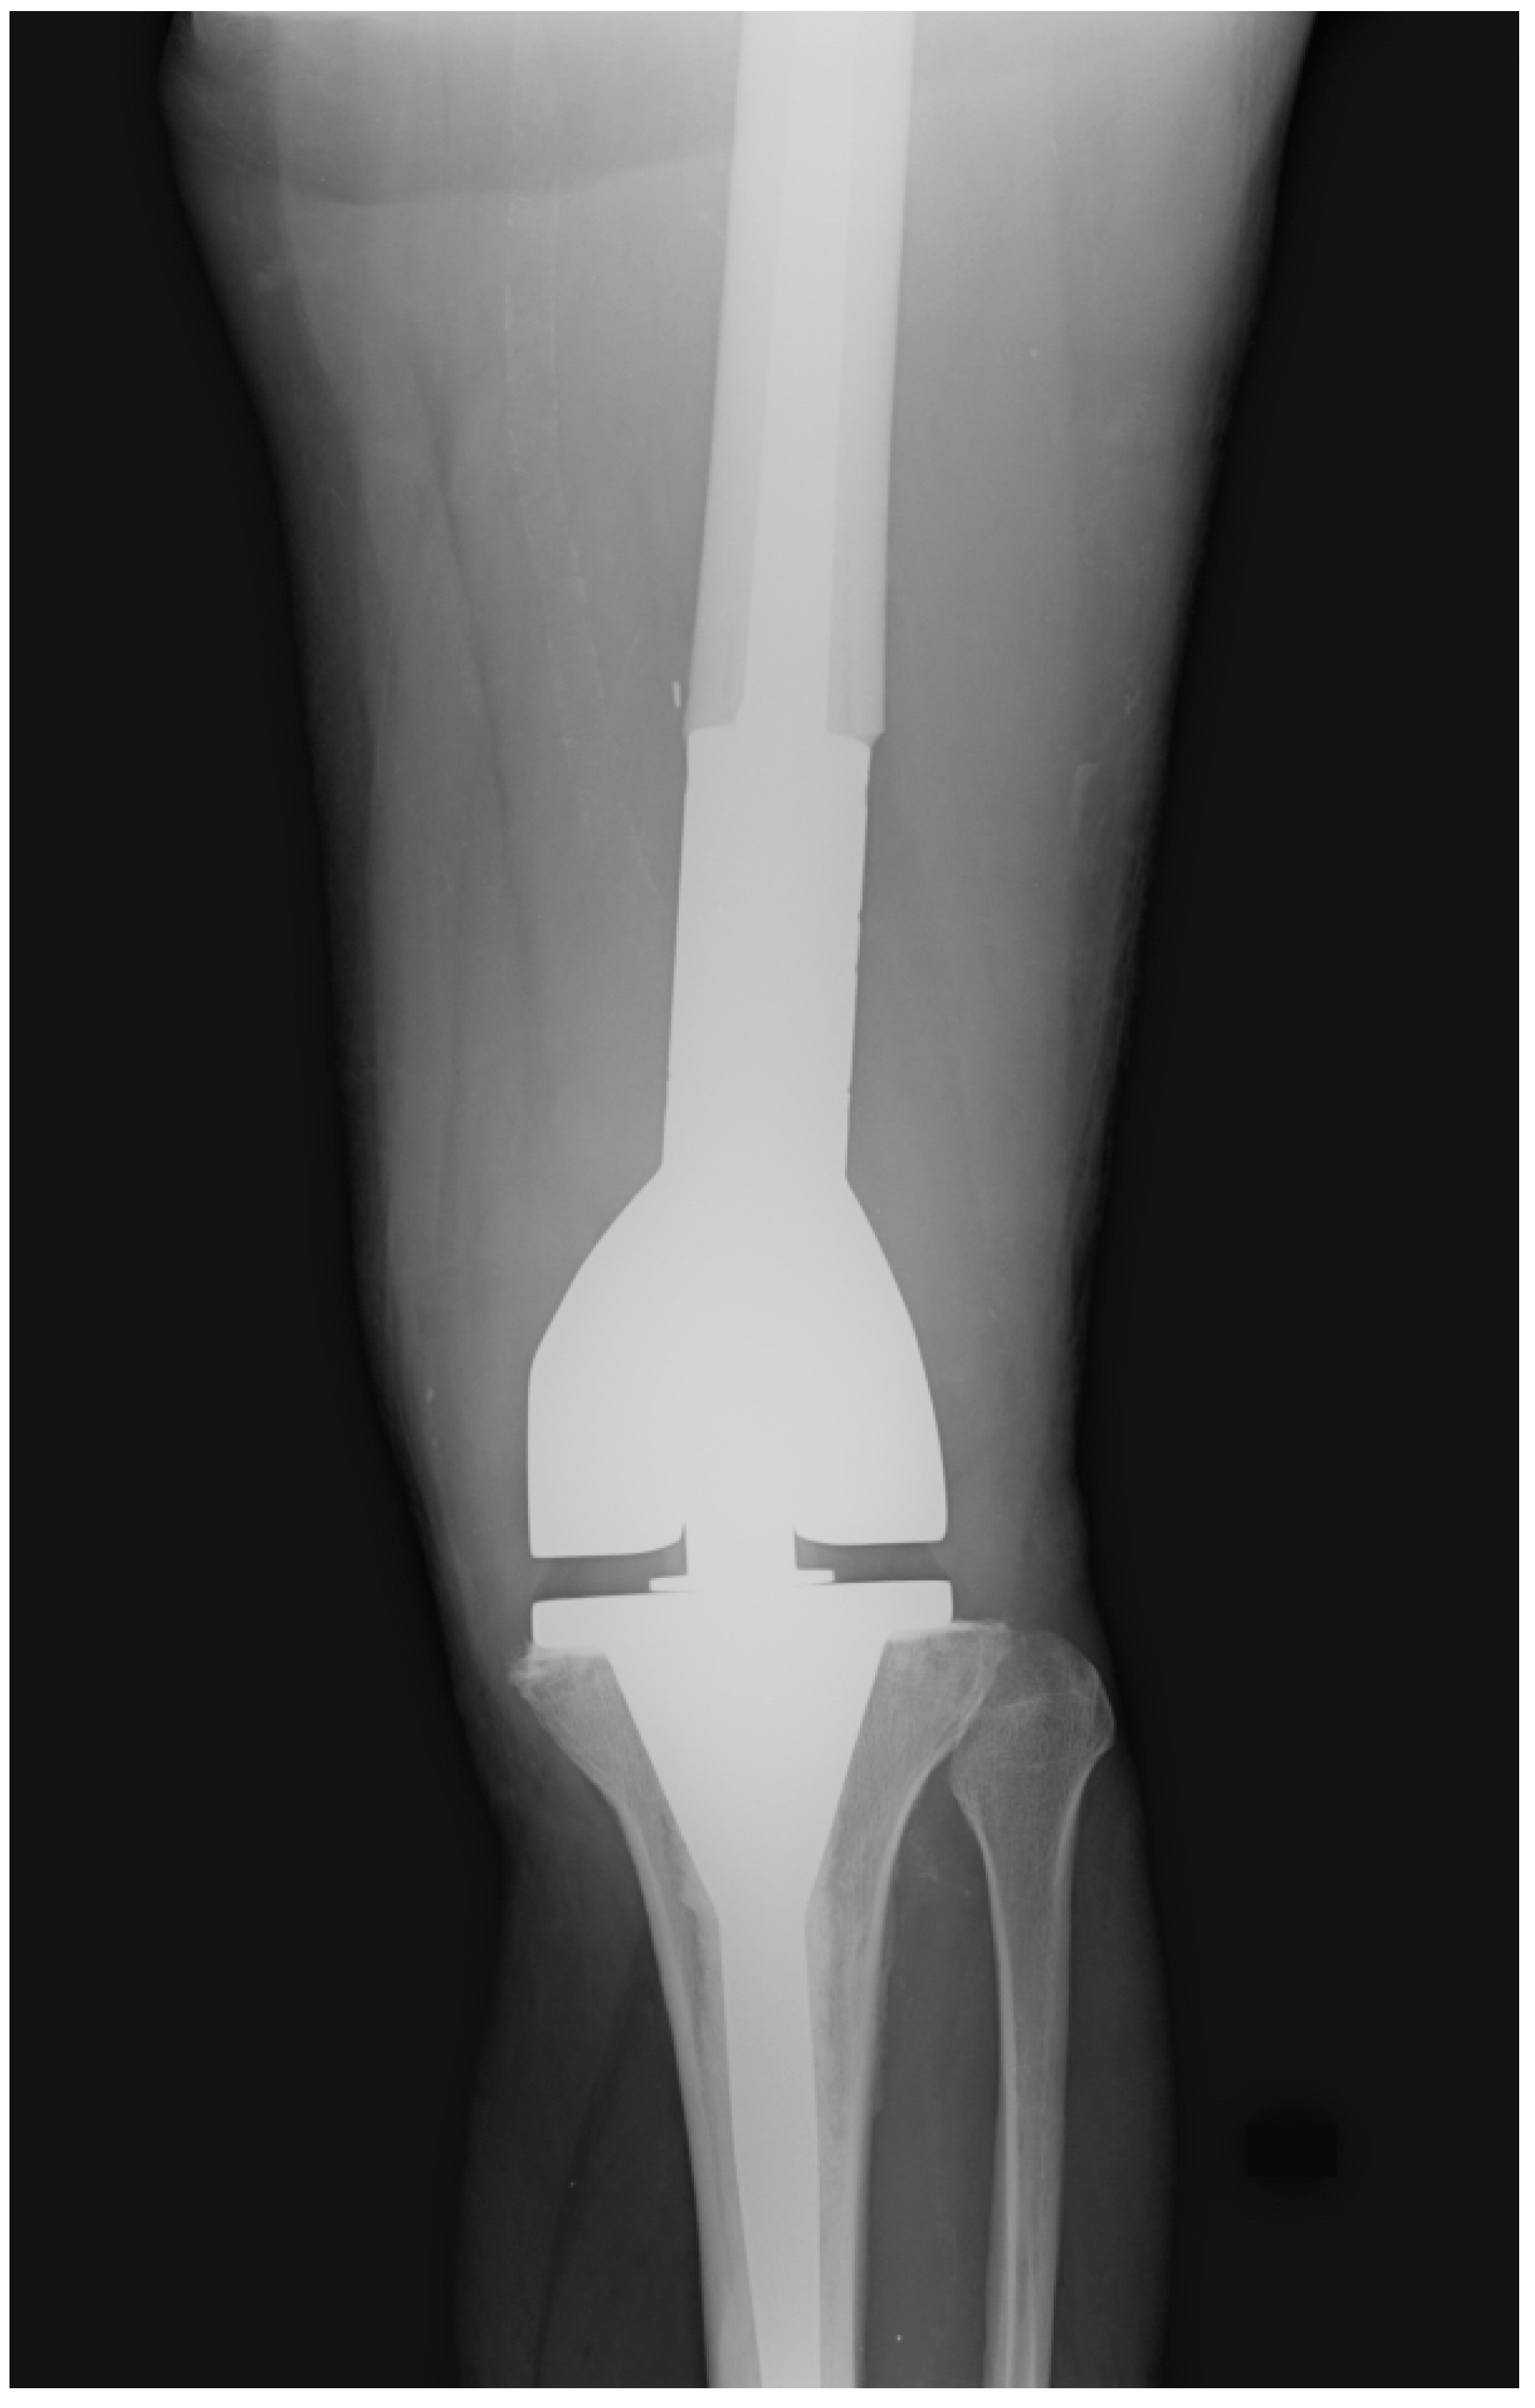

The post-operative follow-up consisted of serial office visits, clinical evaluations, and X-ray images to assess the surgical treatment’s clinical and radiological outcomes (Figure 2).

Figure 2. Post-operative X-ray of one of our patients treated with the implantation of a distal femur megaprosthesis.